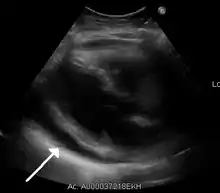

Ultrasounds showing a pericardial effusion in someone with pericarditis

A pericardial effusion as seen on CXR in someone with pericarditis

The diagnosis of tamponade can be confirmed with trans-thoracic echocardiography (TTE), which should show a large pericardial effusion and diastolic collapse of the right ventricle and right atrium. Chest X-ray usually shows an enlarged cardiac silhouette ("water bottle" appearance) and clear lungs. Pulmonary congestion is typically not seen because equalization of diastolic pressures constrains the pulmonary capillary wedge pressure to the intra-pericardial pressure (and all other diastolic pressures).